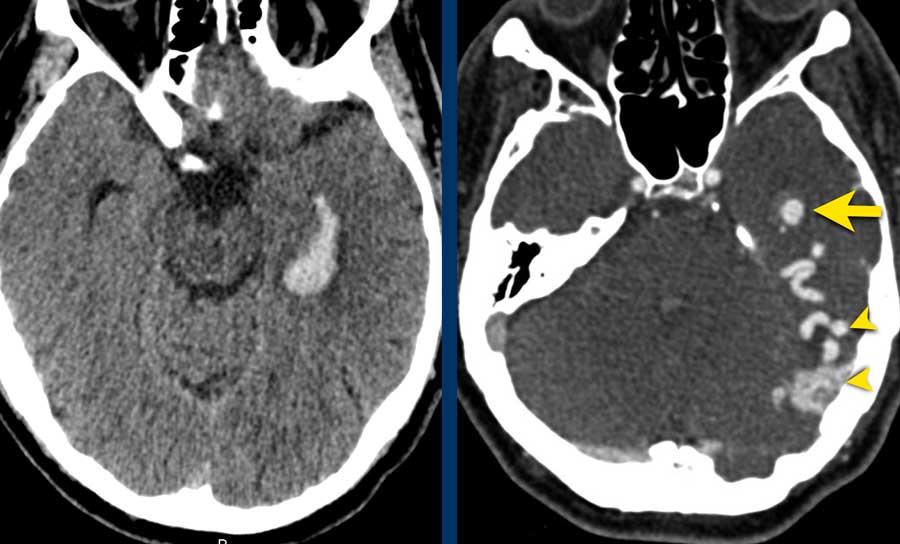

Các hình ảnh thuộc về một bệnh nhân nữ trẻ tuổi với triệu chứng đau đầu khởi phát đột ngột vài giờ sau khi sử dụng cocaine.

Bệnh nhân nhập viện với tình trạng liệt nửa người bên trái.

- A – NCCT cho thấy xuất huyết thùy não ở thùy đỉnh phải với lan rộng vào hệ thống não thất (chấm nhỏ tại lỗ Monroe).

- B – quan sát thấy các tĩnh mạch dẫn lưu lớn.

- C – mũi tên chỉ vào động mạch não giữa phải bị đẩy lên trên do hiệu ứng khối của khối xuất huyết.

- D – quan sát thấy một nidus nhỏ kết nối với các tĩnh mạch bất thường (khá khó nhìn thấy trên CT).